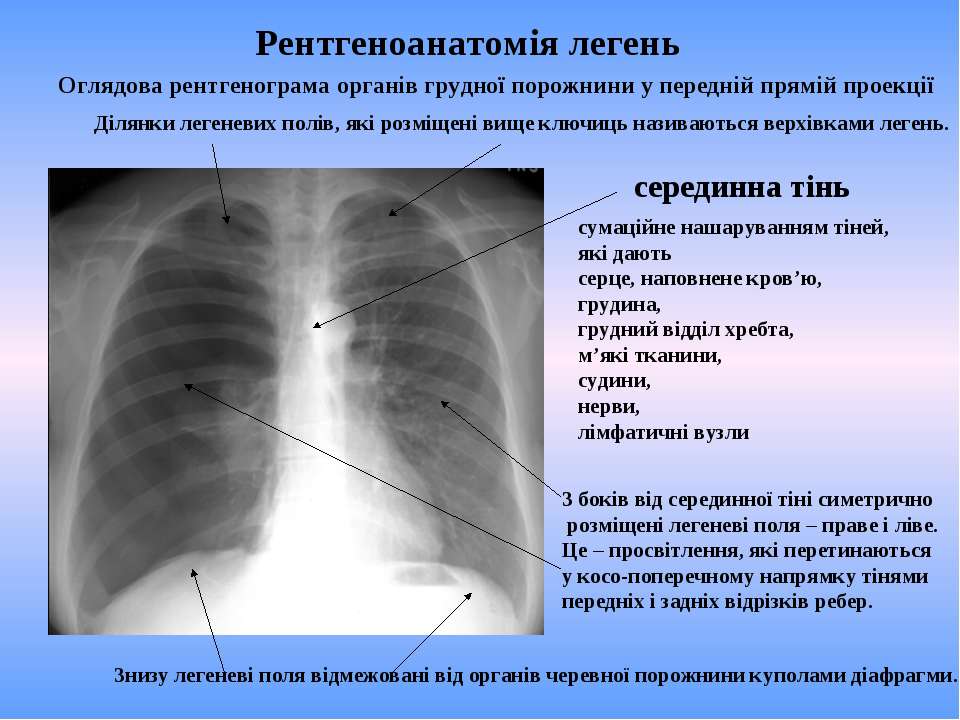

Что такое малоконтрастная рентгенограмма органов грудной клетки